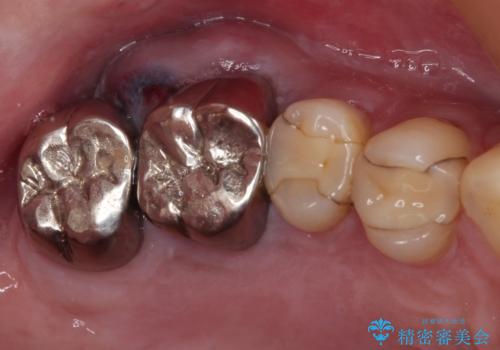

目立つ銀歯と欠けてしまった詰め物 オールセラミッククラウンでの補綴治療